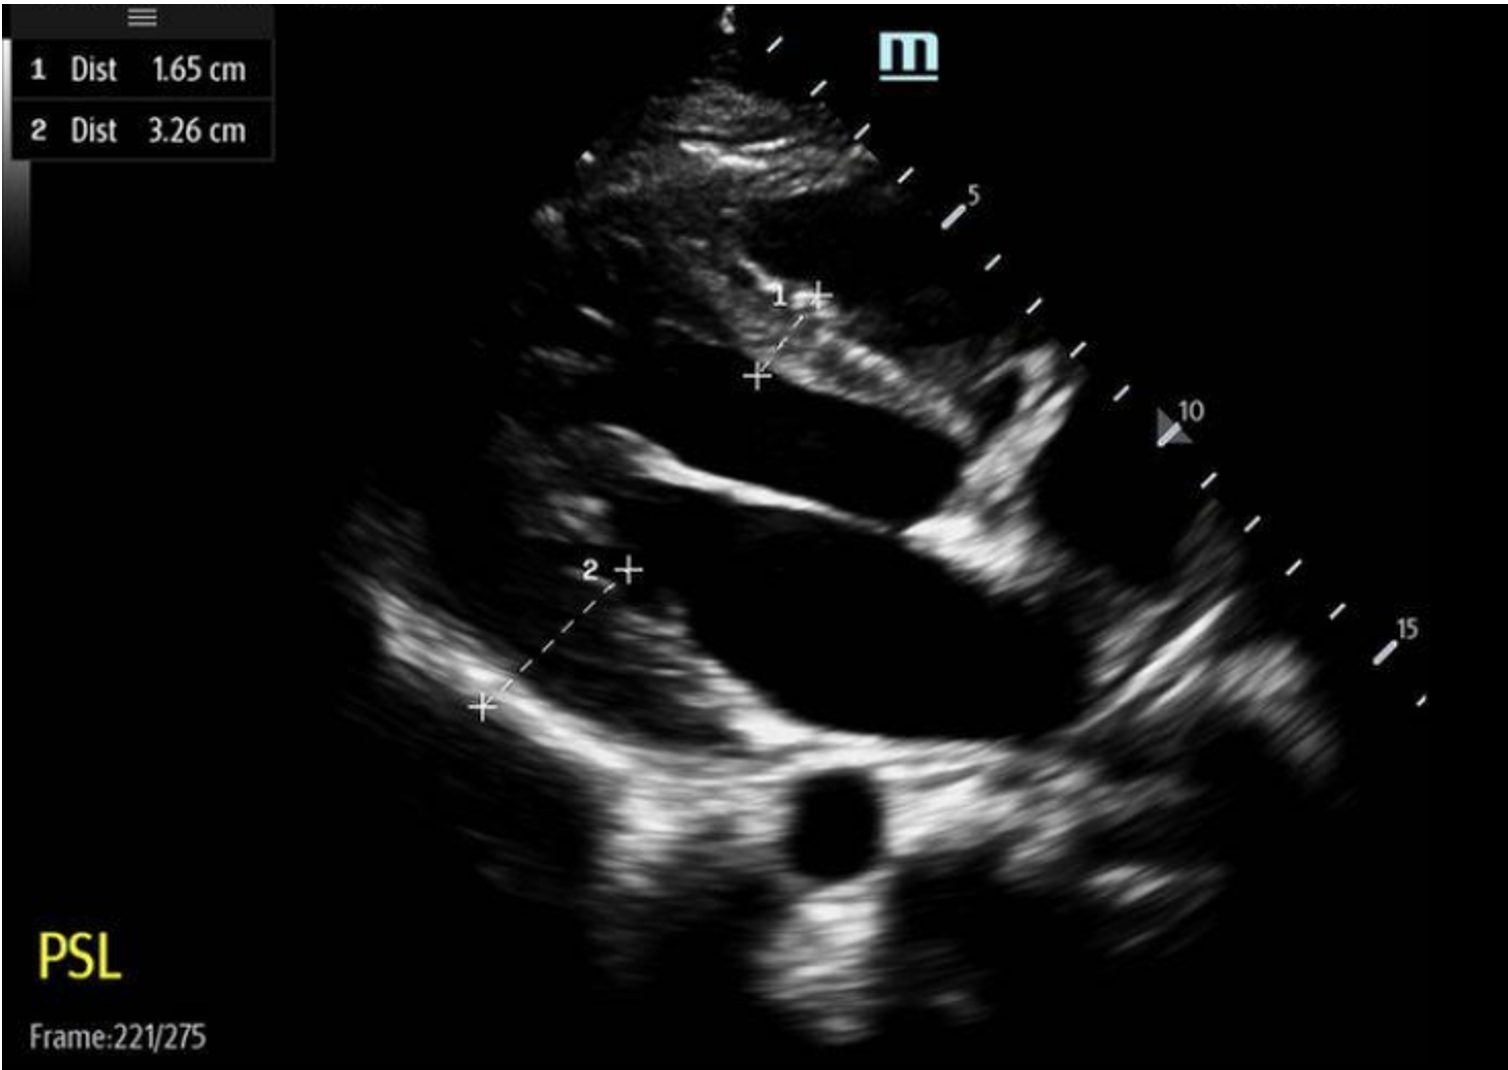

Back to our patient… these were our bedside POCUS findings:

PSL View:

Based on our measurement, the interventricular septal-to-LV wall thickness ratio would be 16.5 mm/32.5 mm = 0.51. This is not consistent with HCM. However, the LV wall thickness is 32.6mm, which would be consistent with HCM.